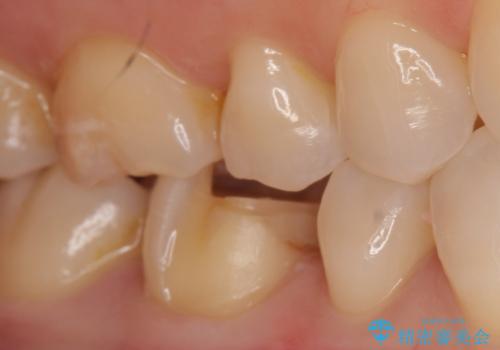

- 過去の樹脂の治療の劣化を治したいとの事で来院。大臼歯の歯は樹脂の範囲が大きくセラミックインレーで処置しても割れてしまう可能性があるため被せ物のご案内をしたところ、なるべく歯を削りたくないとのことでPGAアンレー(ゴールドアンレー)での治療となりました。手前の歯はセラミックの詰め物で治療する事ができました。

歯質の削除量をなるべく最小限にして治療が終わりました。

セラミック、ゴールド共に適合が良く虫歯の再発のリスクが低くなります。